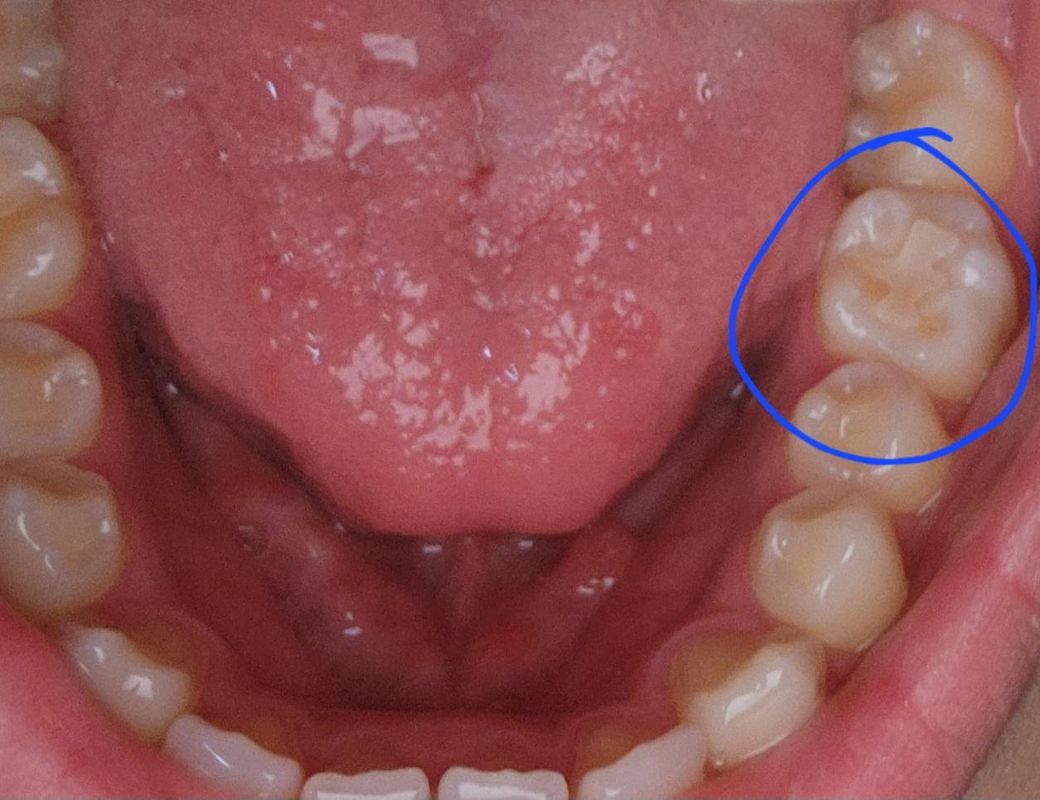

이빨에 노란색 뭔가 있는데 뭔지 모르겠어요

파란색 동그라미 보면 이상한 노란색깔이 있는데 다른 치아에는 없는데 유독 여기에만 있더라구요 이거 뭔가요..? 알려주세욥..ㅠ

예전에 치료를 한 곳이 부분적으로 깨져 나간거 같습니다. 깨진부위에 치아가 노랗게 보이는거 같습니다.

사진으로 보이는 것은 치과용 보철물로 보입니다. 충치로 인해서 충치부위를 제거하고 인레이라고 하는 보철물로 수복을 한상태입니다.

치아가 마모된 부분이 조금 있어보입니다. 충치나 기타 문제가 보이지는 않는 것 같습니다.

씹는면 쪽 말씀하시는거면 마모되어 상아질 드러난거 같고, 치은경계부는 치석 낀것 같습니다